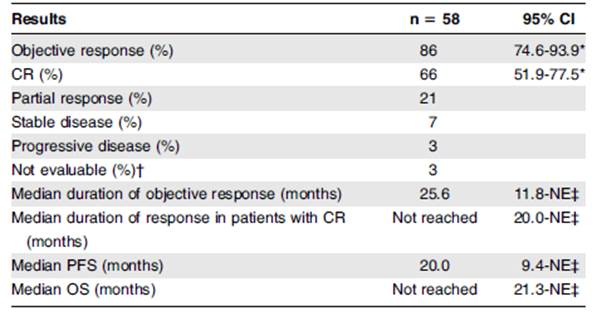

La actividad de BV en ALCL fue claramente documentado por Pro et al. en un ensayo multicéntrico de fase II, donde se trataron 58 pacientes con ALCL sistémico recidivante o refractario (1,8 mg/kg cada tres semanas durante un máximo de 16 ciclos) donde se obtuvo una respuesta global 86% con una tasa de RC del 57% con una mediana de SLP de 13,3 meses(13-14).

Los efectos secundarios graves más comunes (grado 3/4) fueron neutropenia (21%), trombocitopenia (10%) y neuropatía sensorial periférica (10%).

En la actualización de 5 años de Pro et al. las respuestas globales de acuerdo al investigador fueron del 86% y las RC del 66%, (Tabla 2)(15). La duración de respuesta obtenida al BV fue independiente del estatus de ALK (Figura 6).

Tabla 2. Respuesta global y duración de la respuesta por investigador